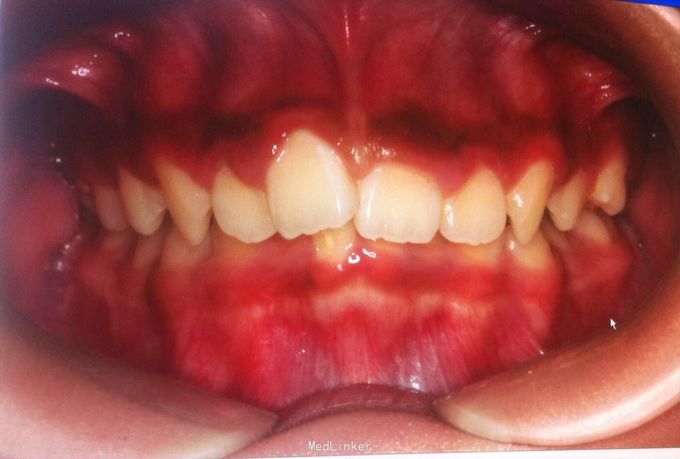

恒牙期 25正锁合 磨牙中性关系 前牙一度深覆盖深覆合 牙列拥挤 张口型异常

安氏一类 不拔牙矫治,直丝弓矫治器,排齐整平上下牙列,治疗后前牙覆合覆盖正常,磨牙中性关系,维持现有面型

面型略凸,若需改善面型,需在治疗中拔除四颗双尖牙